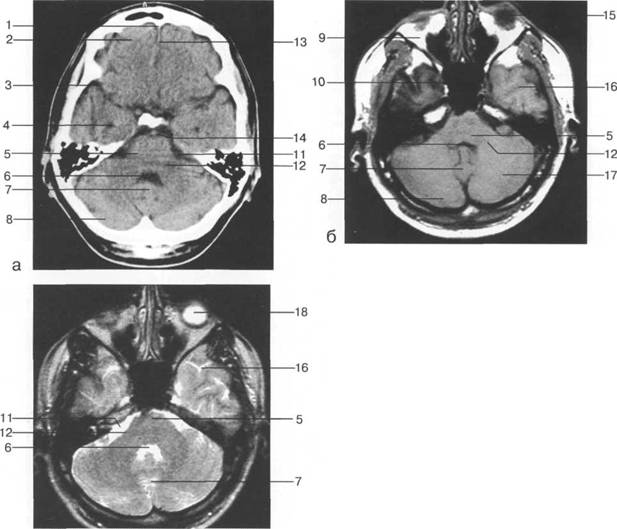

В латеральных отделах дно передней череп 13513u2010n 85;ой ямки образовано крышами глазниц, а в центральном - продырявленной пластинкой. Базальные отделы лобных долей представлены ко

ные извилины (рис. 1.10). Структуры средней череп 13513u2010n 85;ой ямки ограничены спереди малым крылом основной кости, снизу - большим крылом, сзади - передней поверхностью пирами «edge» «bone»

Содержимое средней череп 13513u2010n 85;ой ямки представлено базальными отделами височной доли.

ристый синус с внутренней сонной артерией, череп 13513u2010n 85;о-мозговые нервы) дифференцировать тральные отделы основания череп 13513u2010n 72; занимает турецкое седло. В полости турецкого седла ви